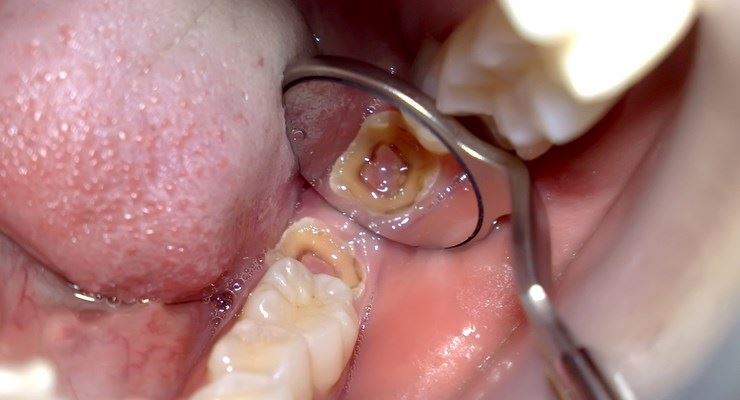

Gigi berlubang?? Memang sakit oi.. kalau tak tampal , nak makan pun seksa tau ! Kebiasaannya, rasa sakit ni muncul disebabkan lubang pada gigi kita dah jadi terlalu dalam hingga menyentuh saraf gigi. Disebabkan itu timbulnya rasa sakit dan perit pada gigi.

Asid ini yang akan membuatkan gigi korang jadi berlubang.. malah lubang akan jadi lagi besar setelah dimasuki sisa makanan. Fuh ini yang buat gigi korang sakit sampai menangkap kepala ni!